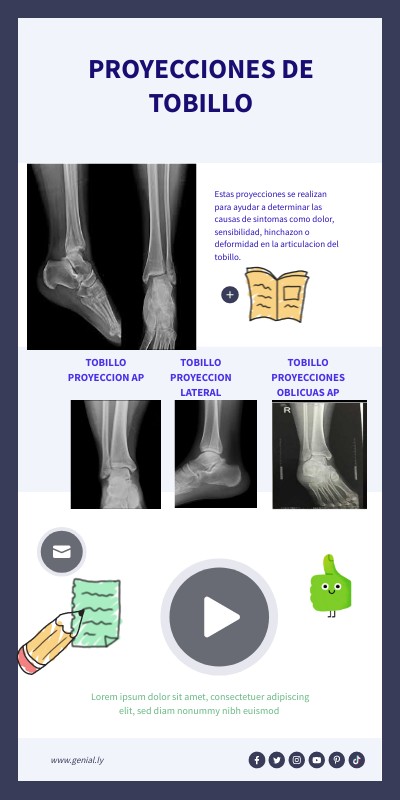

PROYECCIONES DE TOBILLO

Estas proyecciones se realizan para ayudar a determinar las causas de sintomas como dolor, sensibilidad, hinchazon o deformidad en la articulacion del tobillo.

TOBILLO PROYECCION LATERAL

TOBILLO PROYECCION AP

TOBILLO PROYECCIONES OBLICUAS AP